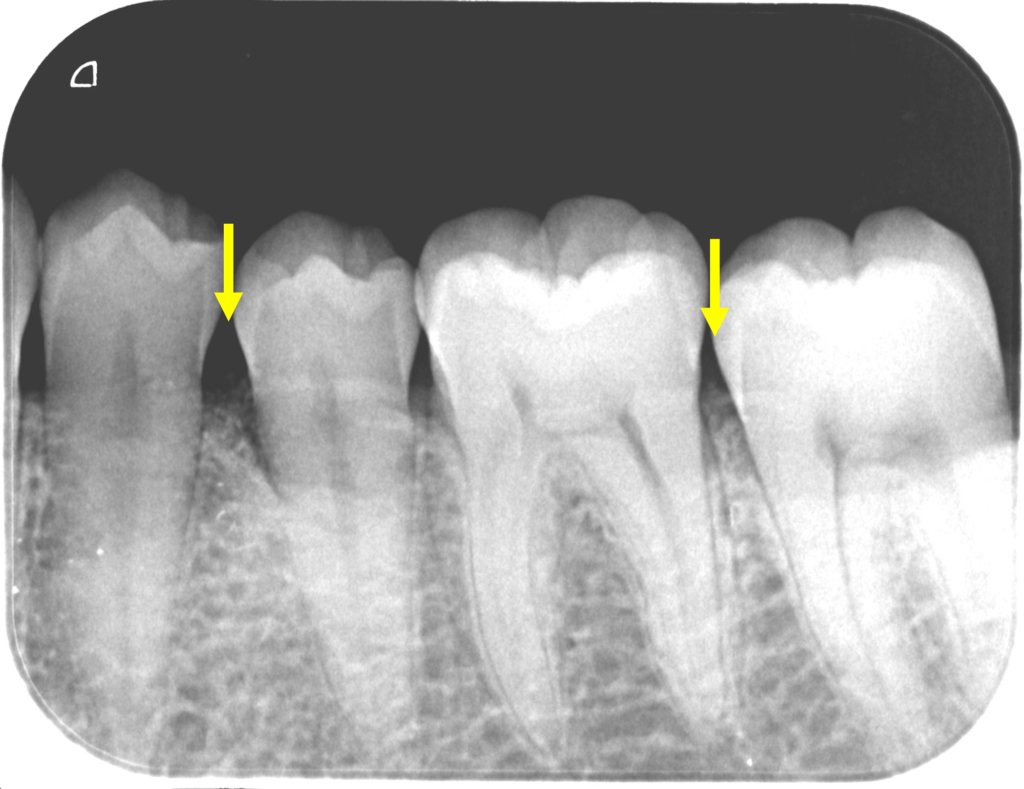

外科後2年です。

骨様組織で骨(歯槽骨)が溶けていた部分が満たされていることが確認できます。

こちらの症例は51歳女性です。

矢印の部分の骨(歯槽骨)が溶けています。

歯肉を開いて歯肉の中の歯根面に付着している歯石や骨(歯槽骨)が溶けている中の不良肉芽(正常でないない軟組織)を徹底的に除去し、

再生材料と人工骨と填入し、縫合しました。